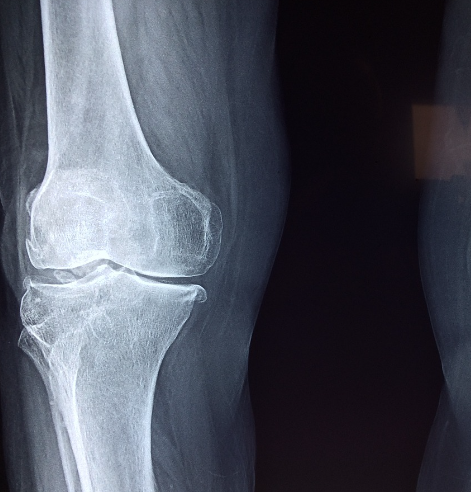

골다공증 수치를 평가하는 주요 지표는 T-스코어와 Z-스코어입니다. 이러한 스코어는 뼈 밀도 검사(Dual-Energy X-ray Absorptiometry, DEXA 스캔)를 통해 측정되며 뼈의 상태와 골다공증의 정도를 판단하는 데 도움이 됩니다.